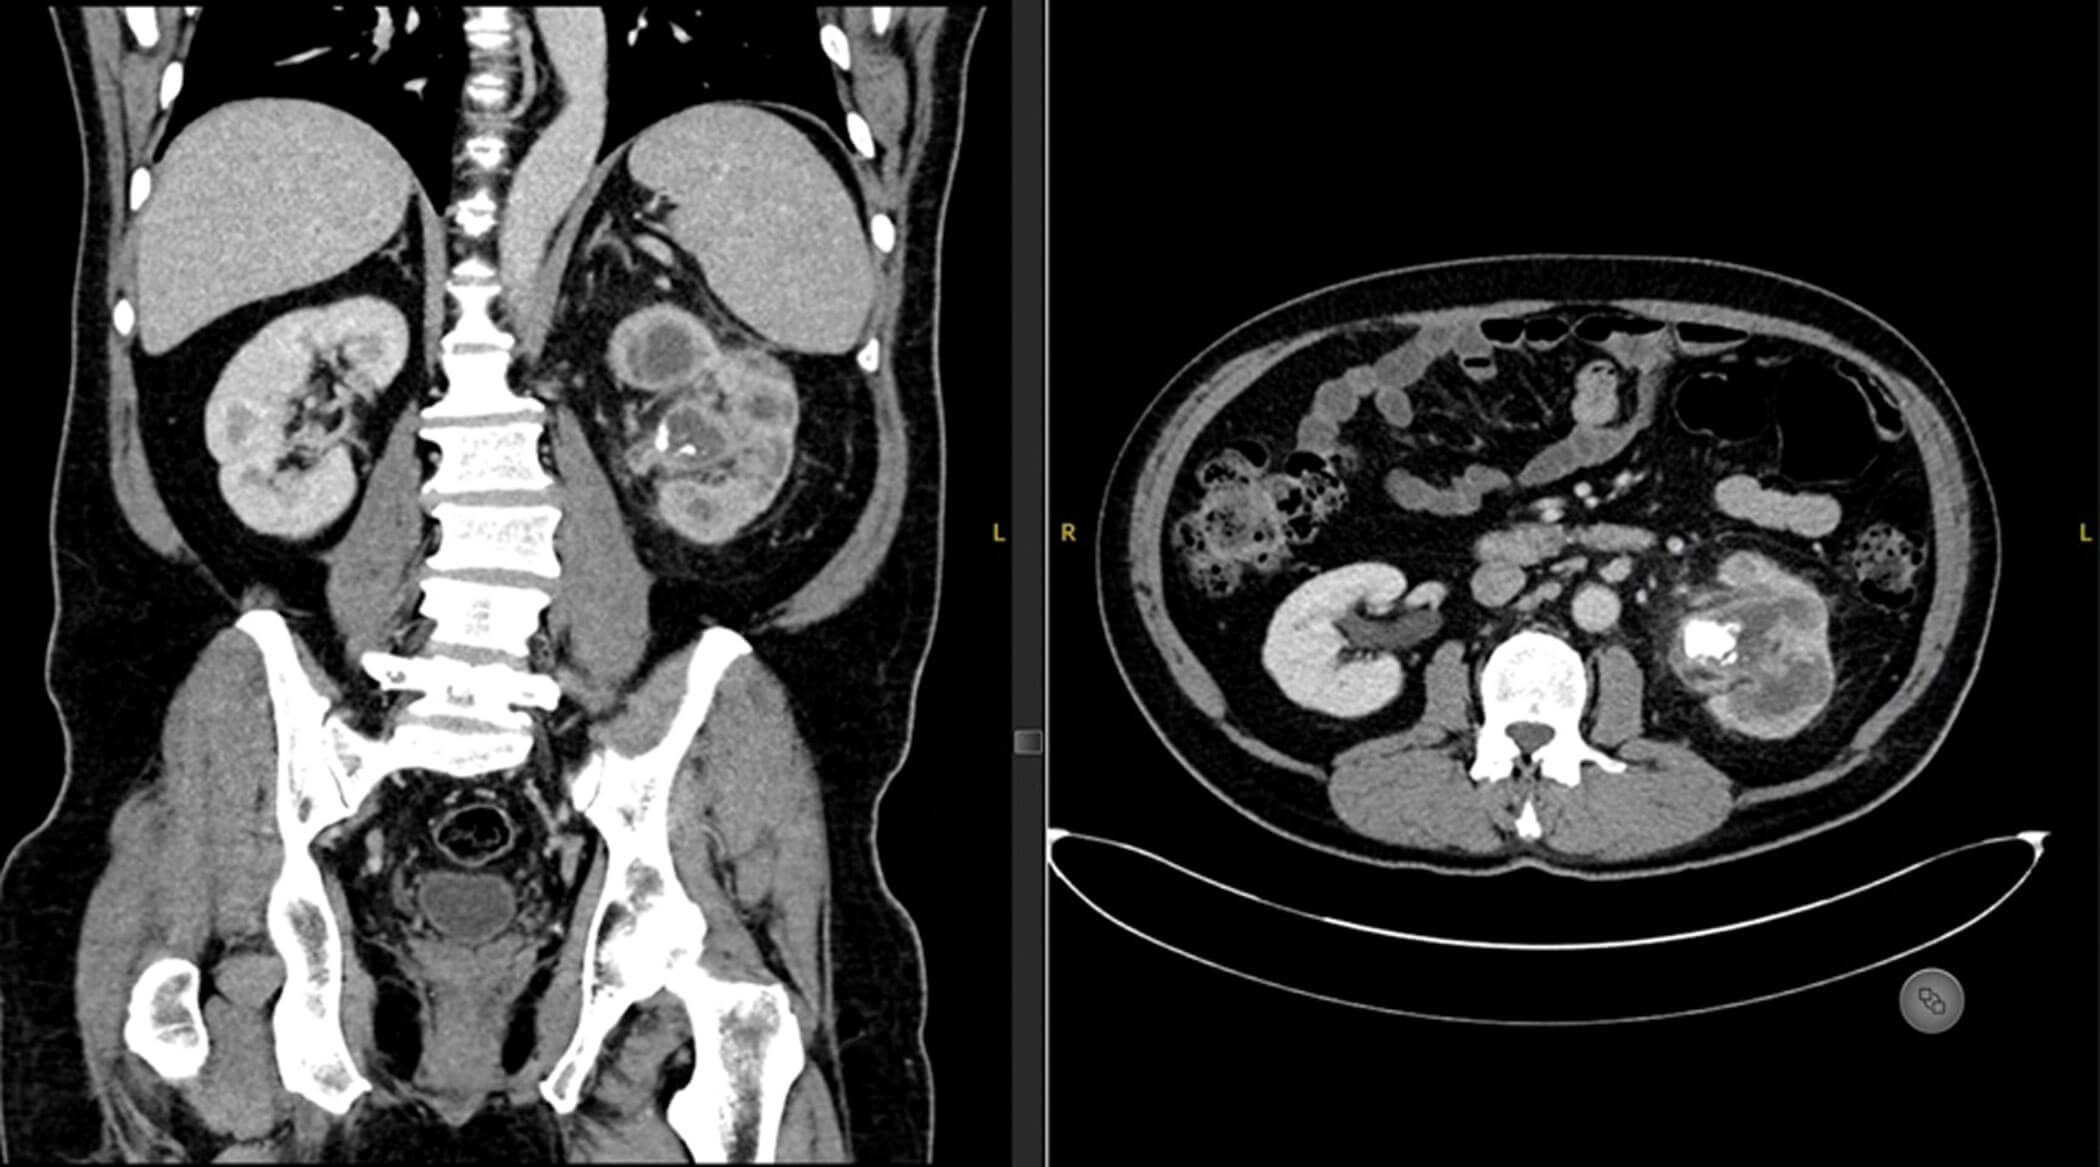

- This is a coronal and axial contrast enhanced CT scan of an abdomen and pelvis. The most striking abnormality is the left 2.5cm PUJ calculus with calyceal dilatation, loss of renal cortex and perinephric inflammation. Additionally, the appearance is consistent with bear’s paw sign. This is xanthogranulomatous pyelonephritis (XGP).

- This is an axial contrast enhanced CT scan of an abdomen and pelvis. The most striking abnormality is a right-sided interpolar renal angiomyolipoma (AML), approximately 3cm in its largest dimension.